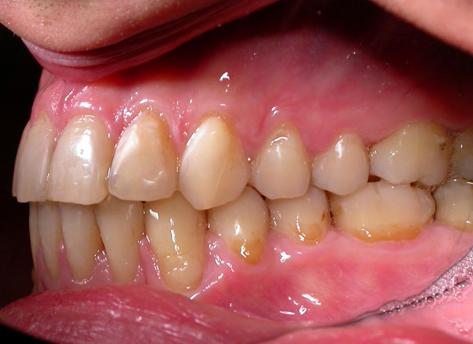

Пациент обратился с диагнозом индивидуальная макродентия.

Диагностика дополнительно выявила:- тенденцию к формированию мезиальной окклюзии,

- сужение и укорочение зубных рядов,

- ретрузию верхних центральных резцов,

- мезиальное смещение боковых отделов нижнего зубного ряда,

- ретрузию нижних резцов,

- множественные аномалии положения зубов.

Лечение проводилось с апроксимальной сепарацией эмали зубов. Применялись керамические брекеты.

Результат получен спустя 18 месяцев после начала лечения